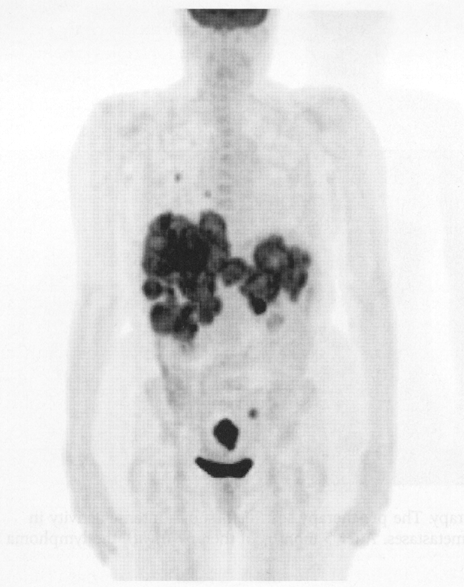

what does this image show

melanoma (scale area)

this image shows what

colon cancer